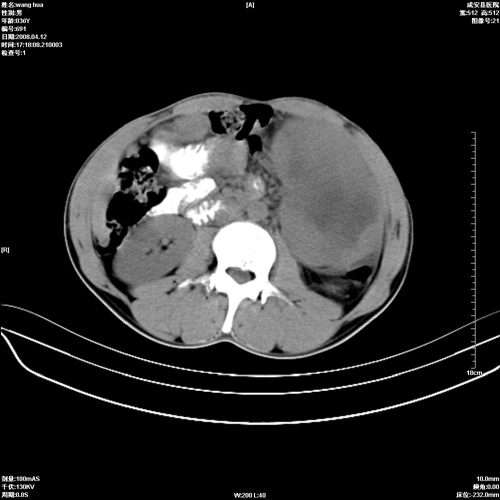

标题: CT12809:男36岁,自感上腹胀5天,B超诊断为脾肾之间占位,血 [打印本页]

标题: CT12809:男36岁,自感上腹胀5天,B超诊断为脾肾之间占位,血

请各位老师先分析一下定位 明天做增强

确实需要强化!先大胆预测一下,来源于脾脏的占位,血管瘤或淋巴瘤可能性大。

脾脏肿瘤,有钙化,增强再说

脾脏明显增大,其内见巨大低密度灶,境界不清,病史较短,考虑恶性病变脾血管内皮细胞肉瘤可能。建议增强扫描与脾脏淋巴瘤及血管瘤鉴别。